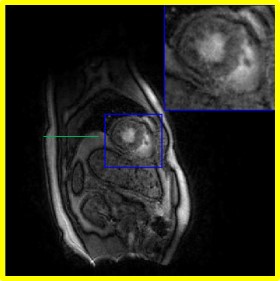

Figure 9: Illustration of the framework of the proposed scheme with d=40𝑑40d=40. We plot the latent variables of 150 frames in a time series on the first dataset. We showed four different phases in the time series: systole in End-Expiration (E-E), systole in End-Inspiration (E-I), diastole in End-Expiration (E-E), and diastole in End-Inspiration (E-I). A thin green line surrounds the liver in the image frame to indicate the respiratory phase. The latent vectors corresponding to the four different phases are indicated in the plot of the latent vectors.

Finally, we illustrate the proposed approaches in Fig. 9 and Fig. 10, respectively. The proposed approach decoupled the latent vectors corresponding to the cardiac and respiratory phases well, as shown in the representative examples in Fig. 9 (a) and Fig. 10 (a).